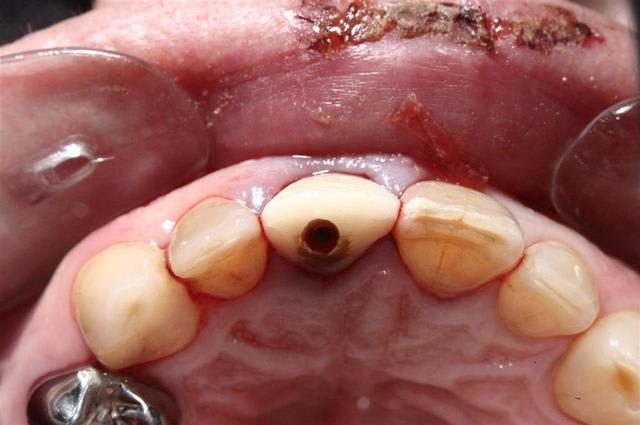

Allez, pour apporter mon caillou à la plage, un cas intéressant, d'implant en urgence.

consultation suite à une chute et fracture de 21 couronnée, un 29 Décembre, décision de poser l'implant le 31.12.

Extraction, mise en place d'un implant de 5*11.5 torque > 35N

Mise en place d'une dent provisoire transvisée.

Prothèse transvisée définitive à 3 mois.

Les 2 dernières photos à 1 an.

la photo ceram en place est à 6 mois. Noter l'amélioration des papilles entre 6 mois et 1 an...

non pas comblé pourtant hiatus assez important environ 1.5mm.

Longueur 11.5, mais j'aurais du mettre un plus long, pour la MCI j'aurais pris moins de risque...